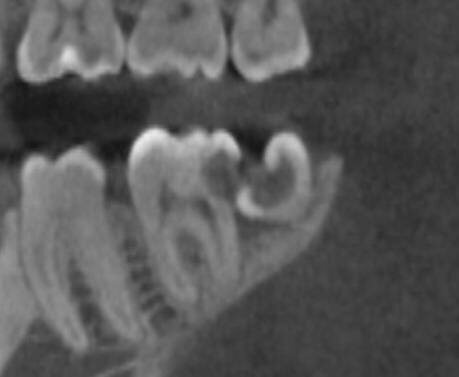

Нижняя восьмёрка, тот самый зуб мудрости, прорезалась одним-единственным бугорком, на фото его даже и не видать. Подленько!

На фото 6 и 7 - 8 даже не видно

Подобно айсбергу, массив тканей 8 зуба так и остался где-то там - как жИрный пИнгвин, в скалах застрявший. Места для нормального прорезывания, как водится, не хватило.

И вот этот одинокий прорезавшийся бугорок создал идеальную ловушку и кормушку для бактерий - глубокое ущелье между восьмым и соседним седьмым зубом. Костный карман со сложными бугристыми стенками, из которого вычистить остатки пищи не способна ни одна щётка в мире и ни один ирригатор. На ёршики тоже не надёйтесь.

Кариес 7 и 8 - срез КТ

Досталось и злосчастной восьмёрке, и ни в чём не повинной семёрке. Во рту эти полости не видны, они спрятаны между зубами, глубоко, у самой десны, уже на корни перешли. Увидеть их можно только на КТ.

На КТ кариозная полость на седьмом зубе выглядит, прямо скажем, устрашающе. Она огромная, инфекционная чернота почти добралась до нерва. И, что особенно неприятно, ушла под десну, затронула корень.